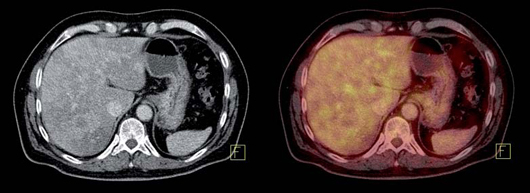

Insulinoma

Es un tumor endocrino del páncreas muy poco frecuente, se calcula su incidencia anual en 0,5-3 casos por millón de habitantes. Casi siempre está ubicado en el páncreas (1/3 en la cabeza, 1/3 en el cuerpo y 1/3 en la cola) aunque puede tener localizaciones ectópicas: duodeno, divertículo de Meckel, vía biliar, ovario y omento. Generalmente son pequeños: 40% son menores de 1 cm y 50% entre 1 y 5 cm y generalmente solitarios. Menos del 10% son múltiples, en cuyo caso debe descartarse síndrome de NEM tipo 1. Menos del 10% son malignos y 5% se presentan con metástasis, generalmente en el hígado o adenopatías regionales27 (Figura 10). Los insulinomas benignos y malignos suelen expresar receptores de somatostatina, el más frecuente es el subtipo 4 (80-90% de los casos), de moderada (10-50%) a gran intensidad (> 50% de las células tumorales) en los estudios inmunohistoquímicos. Los subtipos 1, 2 y 3 se expresan esporádicamente (40-50% de los casos) en los insulinomas benignos y malignos,generalmente en menos del 10% de las células neoplásicas. Los insulinomas benignos no expresan sstr 5 mientras que algunos malignos sí lo hacen28. Estos hallazgos están en línea con la experiencia clínica: aproximadamente el 50% de los insulinomas son positivos en la cintigrafía con pentatreotide y el tratamiento con radiopéptidos análogos de somatostatina (Lu177-DOTATATE o Y90-DOTATOC) es paliativo y sirve para ayudar al control de la hipoglicemia de estos enfermos29 (Figura 11).

Fusión SPECT/RM. Imágenes transaxiales de RM y SPECT con In111- pentatreotide.

Paciente con insulinoma metastásico. Se demuestra intensa sobreexpresión de receptores de somatostatina en metástasis hepáticas múltiples.